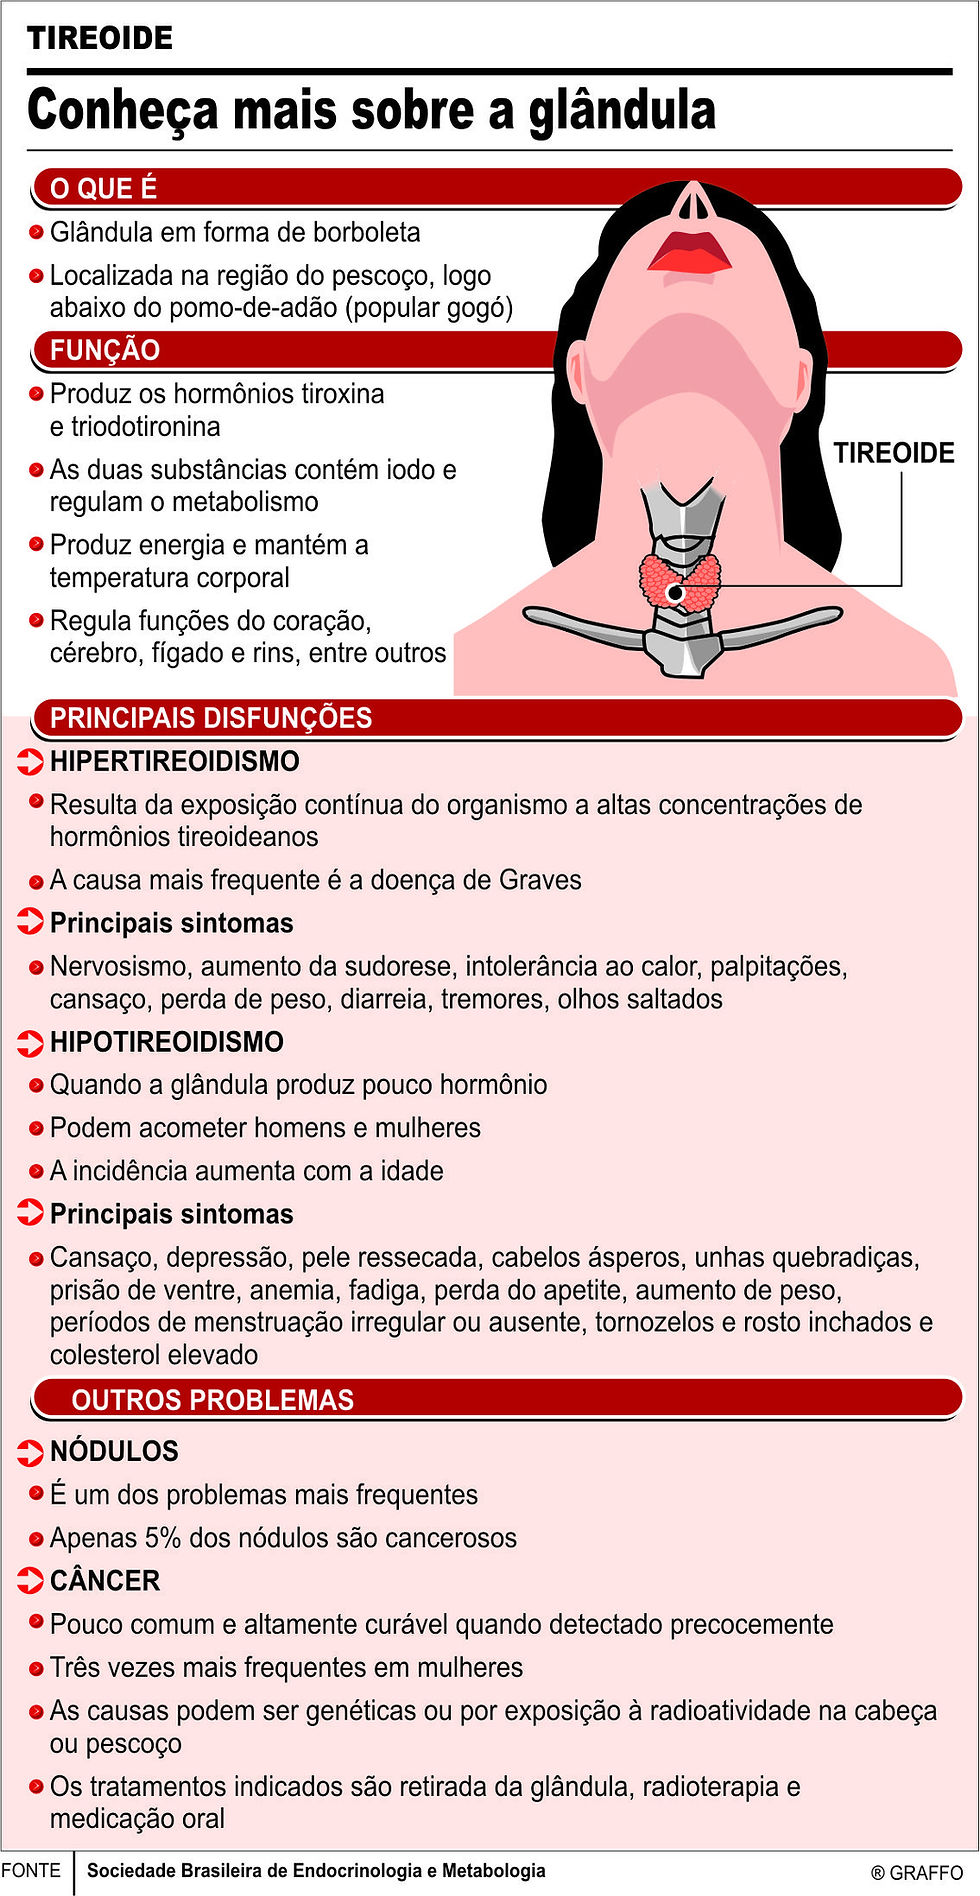

Olha só que interessante: sua tireoide é tipo uma fábrica de hormônios. Para produzir T3 e T4, que são os maestros do seu metabolismo, ela precisa de uma matéria-prima chave: o iodo.

“O iodo é um mineral essencial cuja única função fisiológica conhecida no corpo humano é a síntese dos hormônios tireoidianos (T3 – tri-iodotironina e T4 – tiroxina) pela glândula tireoide, fundamentais para regular o metabolismo e o desenvolvimento de órgãos, especialmente o cérebro.”

Mas não para por aí. O iodo, indiretamente, é um pilar para o bom funcionamento de praticamente todos os sistemas do nosso corpo. Ele está ligado à regulação da temperatura corporal, ao ritmo cardíaco, ao desenvolvimento e maturação de diversos tecidos e, como vamos ver mais adiante, tem um papel que você não pode ignorar no desenvolvimento cerebral.

A tireoide tem um trabalho árduo: produzir os hormônios T3 (triiodotironina) e T4 (tiroxina). E para fazer isso, ela precisa de um parceiro essencial: o iodo. A tireoide capta o iodo do sangue e o utiliza em um processo bioquímico complexo para formar esses hormônios. O T4 tem um átomo de iodo a menos que o T3 e é mais abundante, servindo como um reservatório que pode ser convertido em T3 conforme a necessidade do corpo.

Esses hormônios, T3 e T4, são como os maestros da nossa orquestra metabólica. Eles ditam a velocidade com que nossas células realizam suas funções, influenciando desde a queima de calorias até a produção de proteínas e a manutenção da temperatura corporal. A quantidade de iodo disponível impacta diretamente a capacidade da tireoide de produzir a quantidade certa desses hormônios.

Além do cérebro, o iodo, através dos hormônios tireoidianos, é o maestro do nosso metabolismo. Ele dita a velocidade com que usamos a energia dos alimentos, influencia a temperatura corporal, a frequência cardíaca e até mesmo o nosso humor. Uma tireoide desregulada por falta ou excesso de iodo pode levar a um metabolismo lento (fadiga, ganho de peso) ou acelerado (ansiedade, perda de peso).

Quando o corpo não recebe iodo suficiente, a tireoide entra em ‘modo de alerta’. Ela tenta compensar a falta do mineral trabalhando mais intensamente para captar qualquer iodo disponível e produzir os hormônios necessários. Esse esforço contínuo pode levar ao desenvolvimento de bócio, que é o aumento visível da tireoide no pescoço.

Mas os problemas não param no inchaço. A deficiência crônica de iodo é uma das principais causas de hipotireoidismo, uma condição em que a tireoide não produz hormônios suficientes. Os sintomas podem ser sutis no início, mas incluem fadiga extrema, ganho de peso inexplicável, sensação de frio constante, pele seca, queda de cabelo e, em casos mais graves, atrasos significativos no desenvolvimento cognitivo, especialmente em crianças. A deficiência grave é a causa mais comum de dano cerebral evitável no mundo.

Se a falta de iodo é um problema, o excesso também não fica atrás. Pense na tireoide como um instrumento de precisão: precisa da dose certa. Ingerir quantidades muito elevadas de iodo, especialmente de forma concentrada, pode desregular esse sistema. Um dos riscos é o desenvolvimento de hipertireoidismo, o oposto do hipotireoidismo, onde a tireoide produz hormônios em excesso, acelerando perigosamente o metabolismo.

Outra reação preocupante é o chamado efeito Wolff-Chaikoff. Nesse cenário, uma alta dose de iodo pode, paradoxalmente, ‘bloquear’ temporariamente a produção hormonal da tireoide. Isso pode levar a um quadro de hipotireoidismo transitório ou, em pessoas suscetíveis, desencadear inflamações e disfunções tireoidianas, incluindo doenças autoimunes. A deficiência de iodo pode levar ao bócio, hipotireoidismo, fadiga e atrasos no desenvolvimento cognitivo, mas o excesso também traz seus perigos.